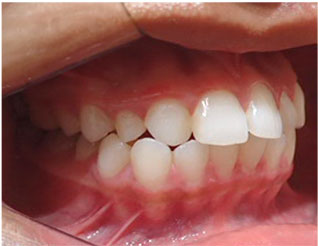

この方は上下の歯並びが全体的に悪い状態でした。

クリアコレクト矯正というマウスピース矯正で治しました。

期間は2年でした。